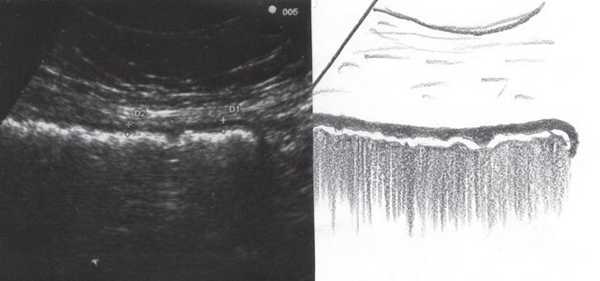

С подозрением на дивертикулит больная была направлена на срочное ультразвуковое исследование (УЗИ) органов брюшной полости, почек и органов малого таза. Исследование было выполнено на современном аппарате конвексным датчиком 3,5 МГц, линейным датчиком 7,5 МГц и эндовагинальным датчиком с переменной частотой 5,0-7,5 МГц с использованием цветового и энергетического допплеровского картирования.

При УЗИ были выявлены диффузные изменения печени и поджелудочной железы, признаки хронического бескаменного холецистита, ангиомиолипома левой почки (без динамики за несколько лет), состояние после экстирпации матки с придатками. В левой подвздошной области соответственно зоне максимальной пальпаторной болезненности на протяжении 9 см отмечалось утолщение стенок толстой кишки до 6-7 мм (рис. 1). Перистальтика кишки отсутствовала, гаустрация была слабо выражена, при этом визуализировалось несколько болезненных при надавливании датчиком выпячиваний пониженной эхогенности, размером от 7 до 20 мм (рис. 2, а, б) с тонкой стенкой до 0,9-1,1 мм и наличием в некоторых из них фрагментов кишечного содержимого и газа (рис. 3, а, б).

Рис. 1. Эхографическая картина дивертикулита. Трансабдоминальное исследование линейным датчиком 7,5 МГц.

"Симптом пораженного полого органа".

Рис. 2. Эхографическая картина дивертикулита. Трансабдоминальное исследование линейным датчиком 7,5 МГц.

а) Продольный срез.

б) Поперечный срез.